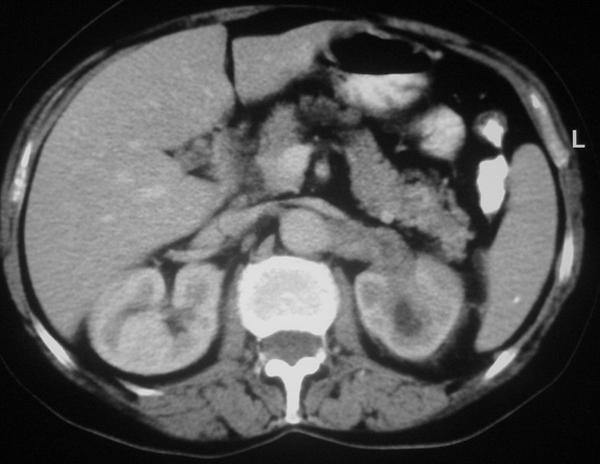

We present a case of a 68-year-old woman who underwent a computed tomography scan of the abdomen in the work-up for recently diagnosed hypertension. A non-enhancing left renal sinus mass was detected extending to the para-aortic space. The initial diagnosis was that of a tumor of the collecting system. Nephro-ureterectomy was performed and the pathology results revealed changes of chronic pyelonephritis.

我们呈现了一例68岁女性患者,其因近期诊断为高血压而接受腹部计算机断层扫描。检查发现一个无强化的左肾窦肿块延伸至腹主动脉旁间隙。初步诊断为集合系统肿瘤。实施了肾输尿管切除术,病理结果显示为慢性肾盂肾炎改变。